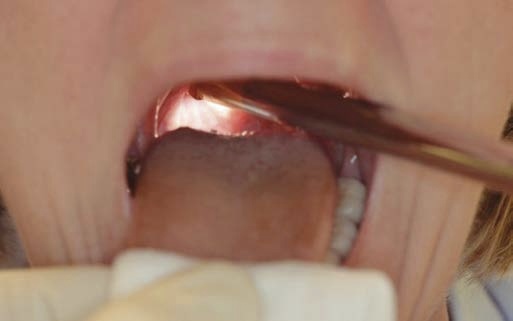

Problem: The Uvula Disturbs

The uvula may intrude and disturb adequate illumination during rigid endoscopy.

When the endoscope lens is placed very close to a surface, the image will show a local washed-out whitish patch due to the camera’s averaging light management software.

Solution:

When “fighting” with the uvula, try dropping the endoscope tip and advancing it a bit more inferiorly.